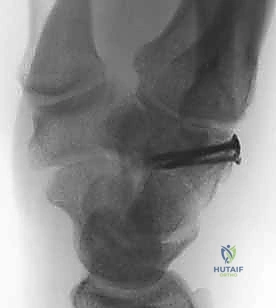

* أسلاك كيرشنر (K-wires): أسلاك معدنية دقيقة يتم إدخالها عبر الجلد لتثبيت عظم المشط بعظام الرسغ المجاورة. تُزال هذه الأسلاك في العيادة بعد 4 إلى 6 أسابيع.

* الشرائح والمسامير الدقيقة (Mini-Plates & Screws): في حالة الكسور المفتتة جداً، يستخدم الدكتور شرائح من التيتانيوم متناهية الصغر لتثبيت الكسر بشكل دائم وقوي، مما يسمح بحركة مبكرة لليد.

الخطوة الرابعة: التثبيت الداخلي (Internal Fixation)

وهنا تبرز مهارة الجراح. يعتمد نوع التثبيت على شكل الكسر: